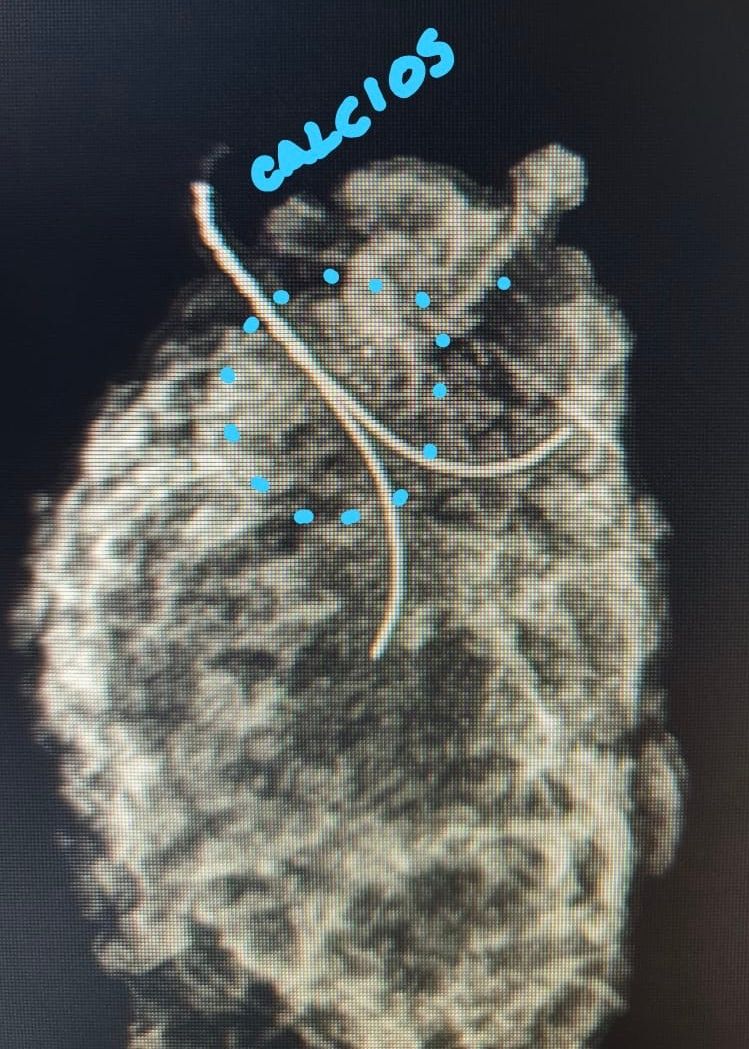

Tratamiento para acretismo placentario